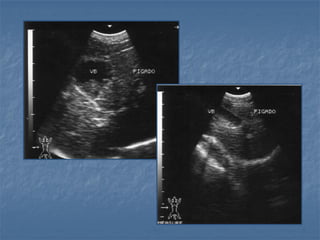

Obstrução Biliar Extra-Hepática

Obstrução vias biliares extra hepáticas

sem dilatação da vesícula biliar

felino